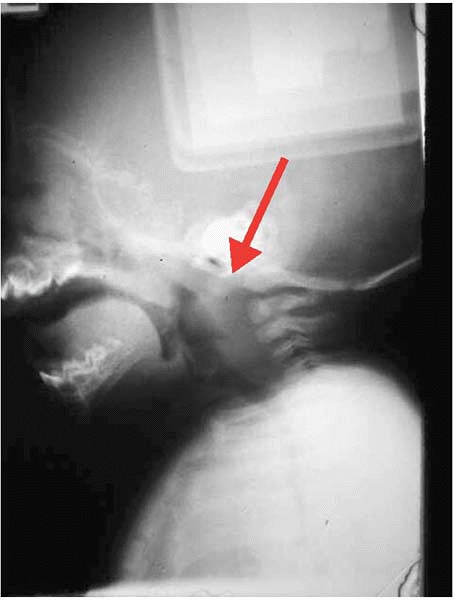

![]() |

|

▪ FIGURE 4-3

Increasingly over the past decade, MRI has become an important tool to avoid trouble when caring for a child with a possible occult cervical spine injury. MRI is particularly valuable to clear the cervical spine of a child who cannot cooperate with voluntary flexion and extension radiographs. This image allowed the diagnosis of ligamentous disruption at the occipitocervical junction (red arrow). |

victims are head injury and intraabdominal hemorrhage. One of the most

important ways to stay out of trouble as an orthopaedist caring for

severely injured children is establishing a good relationship with your

neurosurgeon, and using a careful physical exam with liberal use of

imaging (Fig. 4-3), are valuable ways to optimally collaborate care when there are both skeletal injuries and multiple internal injuries.